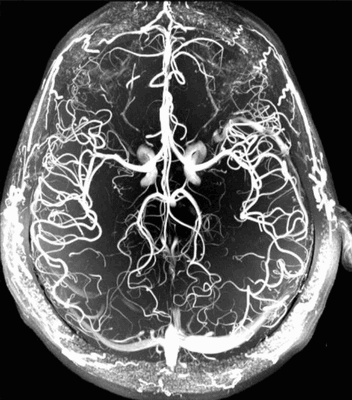

3D-модель церебральных артерий и вен

На фоне ядерного резонанса возникает слабый электромагнитный сигнал, который считывают при помощи чувствительных детекторов. Информацию обрабатывают, данные преобразуют в серию послойных снимков и транслируют на монитор компьютера.

МРТ сосудов головного мозга включает сканирование вен и артерий, изучение характера церебрального кровоснабжения. Объект исследования обладает выраженными парамагнетическими свойствами. Благодаря высокому содержанию воды жидкие среды обеспечивают гиперинтенсивный сигнал на фоне окружающих тканей. При необходимости МРТ артерий головного мозга можно проводить без использования контраста.

С помощью магнитно-резонансной томографии получают подробные изображения всей артериальной системы головы или определенного участка интракраниального пространства. На снимках хорошо видны сосуды и окружающие ткани.